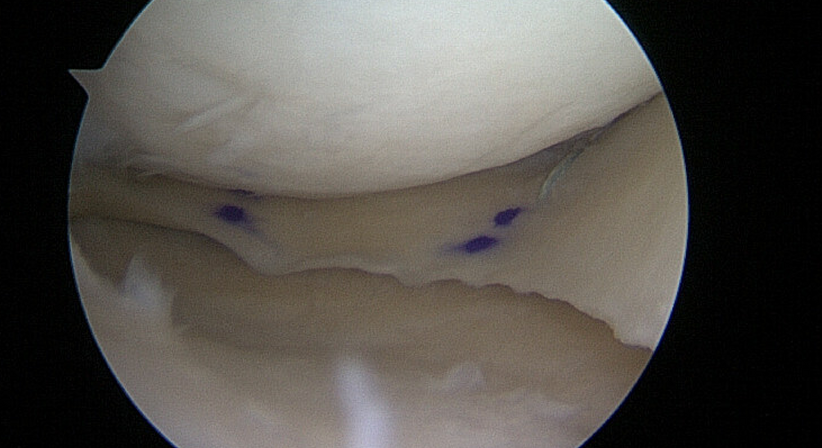

Die Operation wird von mir arthroskopisch (Schlüsselloch-Chirurgie) mit nur kleinsten Hautinzisionen durchgeführt.